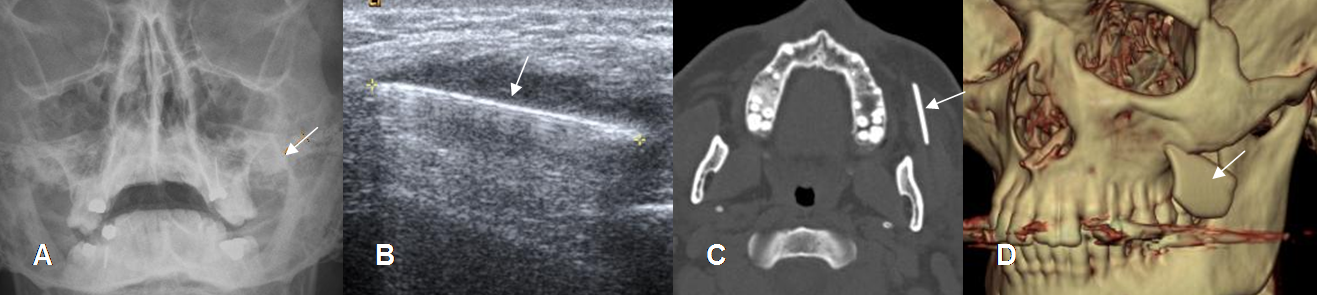

Fig 211. Cuerpo extraño. Paciente con antecedente de trauma abierto en la cara.

A: Rx AP. Imagen lineal y densa.

B: Ecografía. Imagen ecogénica con hiper-refringencia posterior.

C: TAC axial y D: TAC reconstrucción en 3D. Imagen densa proyectada por debajo del hueso malar, que corresponde a cuerpo extraño. (Vidrio).